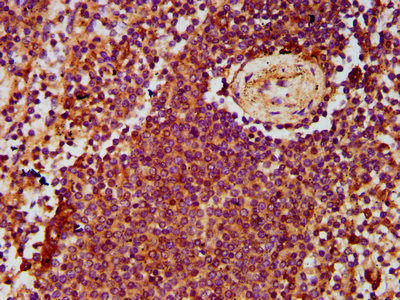

IHC image of CSB-PA887050LA01HU diluted at 1:500 and staining in paraffin-embedded human lymph node tissue performed on a Leica BondTM system. After dewaxing and hydration, antigen retrieval was mediated by high pressure in a citrate buffer (pH 6.0). Section was blocked with 10% normal goat serum 30min at RT. Then primary antibody (1% BSA) was incubated at 4°C overnight. The primary is detected by a biotinylated secondary antibody and visualized using an HRP conjugated SP system.